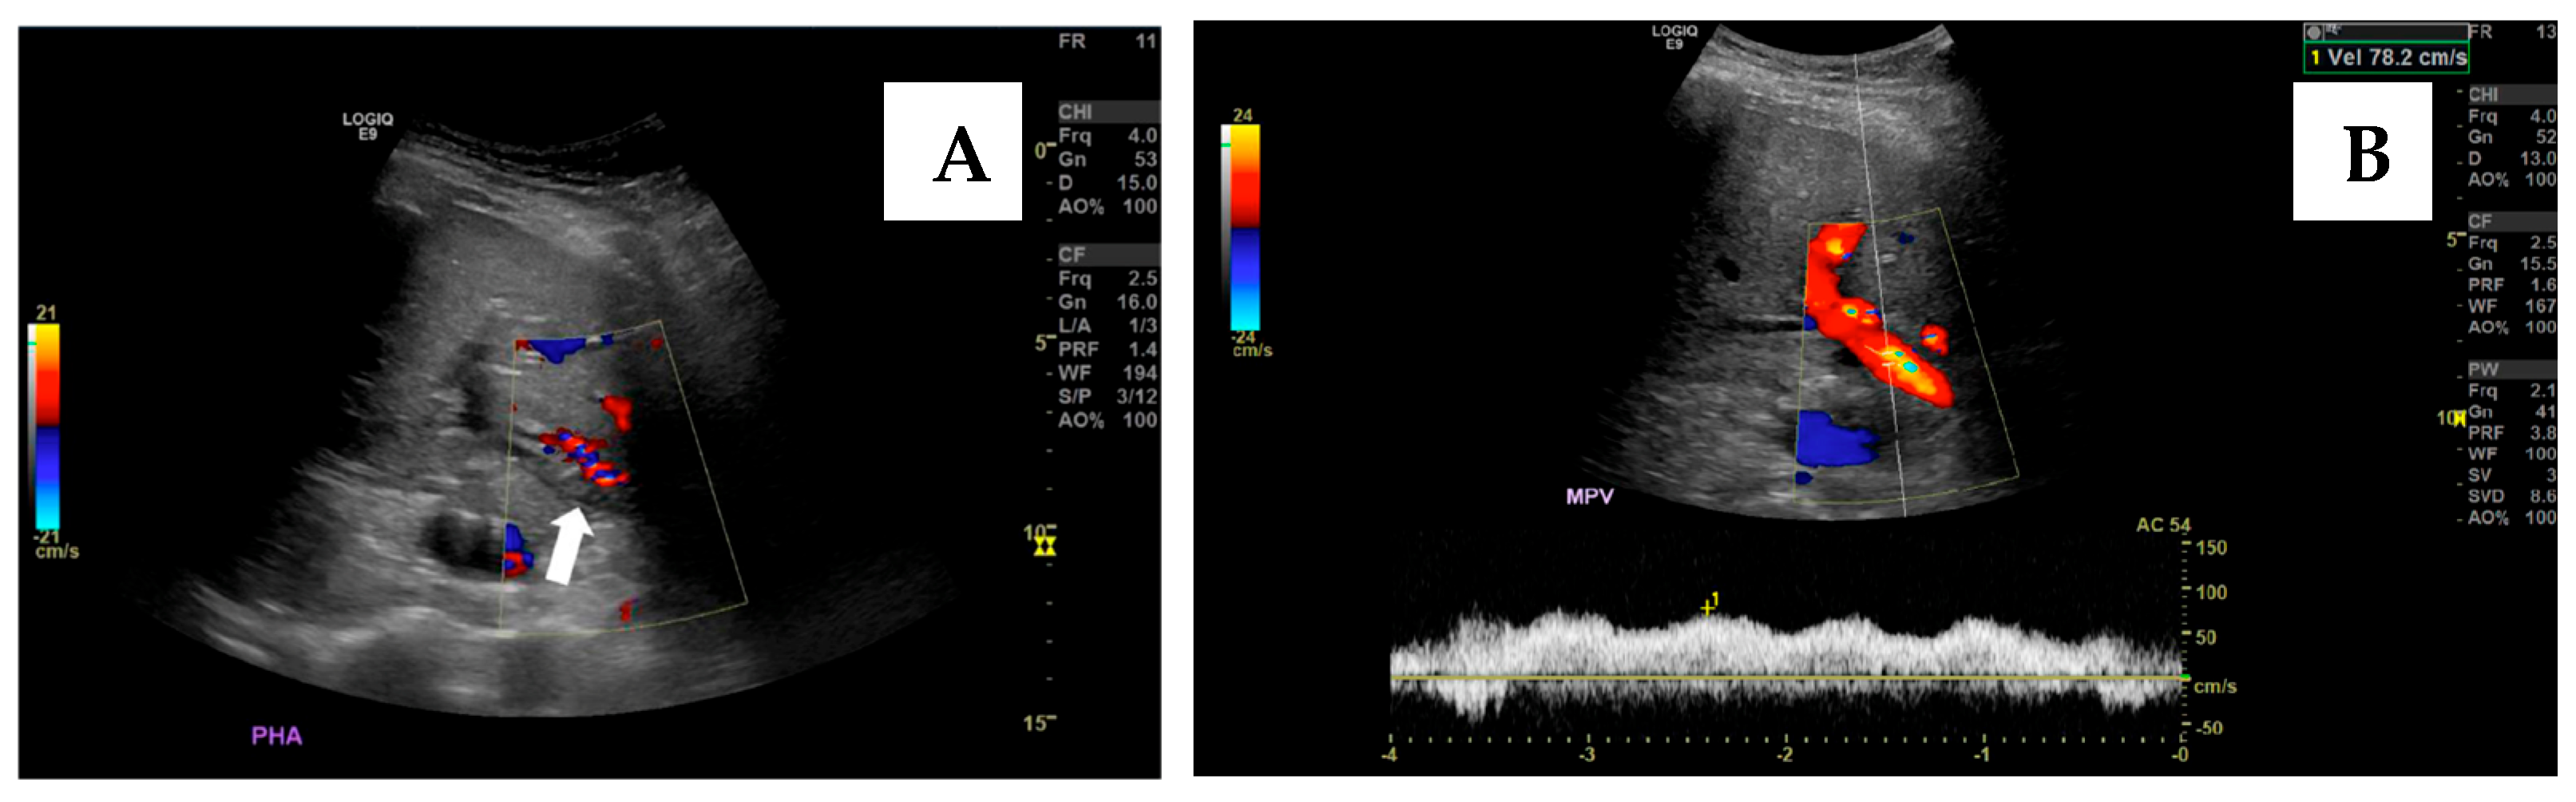

- Brown, M.A.; Donahue, L.; Gueyikian, S.; Hu, J.; Huffman, S. Endovascular transsplenic recanalization with angioplasty and stenting of an occluded main portal vein in an adult liver transplant recipient. Radiol. Case Rep. 2020, 15, 615–623. [Google Scholar] [CrossRef] [PubMed]

- Zhu, K.; Meng, X.; Zhou, B.; Qian, J.; Huang, W.; Deng, M.; Shan, H. Percutaneous transsplenic portal vein catheterization: Technical procedures, safety, and clinical applications. J. Vasc. Interv. Radiol. 2013, 24, 518–527. [Google Scholar] [CrossRef]